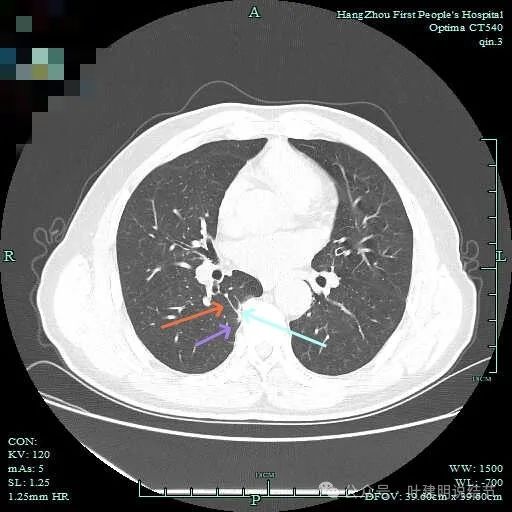

右下脊柱旁怎么也像有磨玻璃结节?但此处正常CT也是略显有慢性炎似的征象的,可这个病人明显结节状,还表面有细毛刺似的。

紧贴脊柱处混合密度,趴在脊柱上,这不像结节状。

但有小血管似的,磨玻璃部分界限较清。但此类异常影像在正常人的CT上也挺常见。

密度较高,确实像血管进入。但病灶片状,趴在脊柱上。